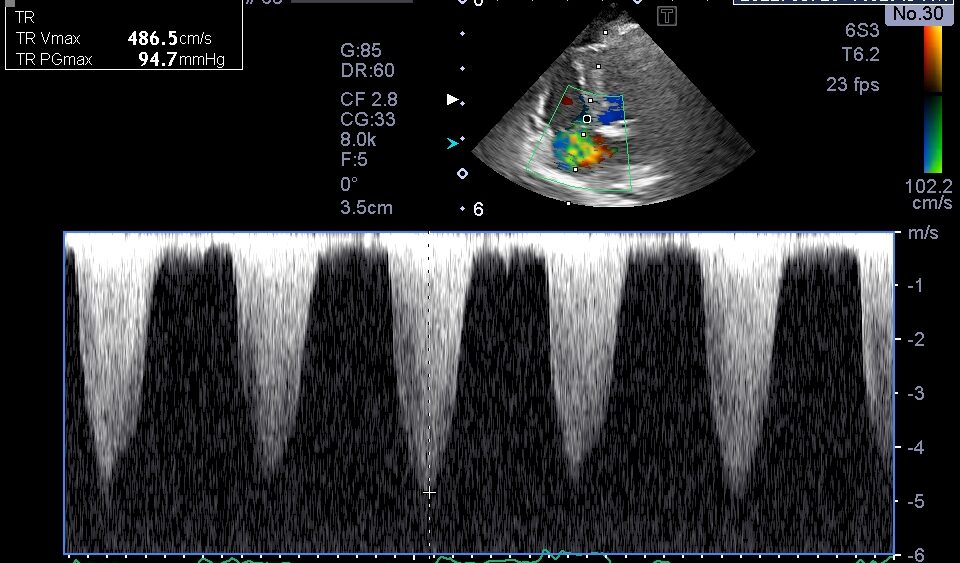

重度の三尖弁逆流

胸部超音波検査では、上記のような肺高血圧症による心臓の変化が認められました。

これらの所見から、現在の投薬では肺高血圧症のコントロールが難しいと判断し、利尿剤の追加とシルデナフィルの増量を行いました。

以前と比較して、三尖弁逆流速度の低下を認める